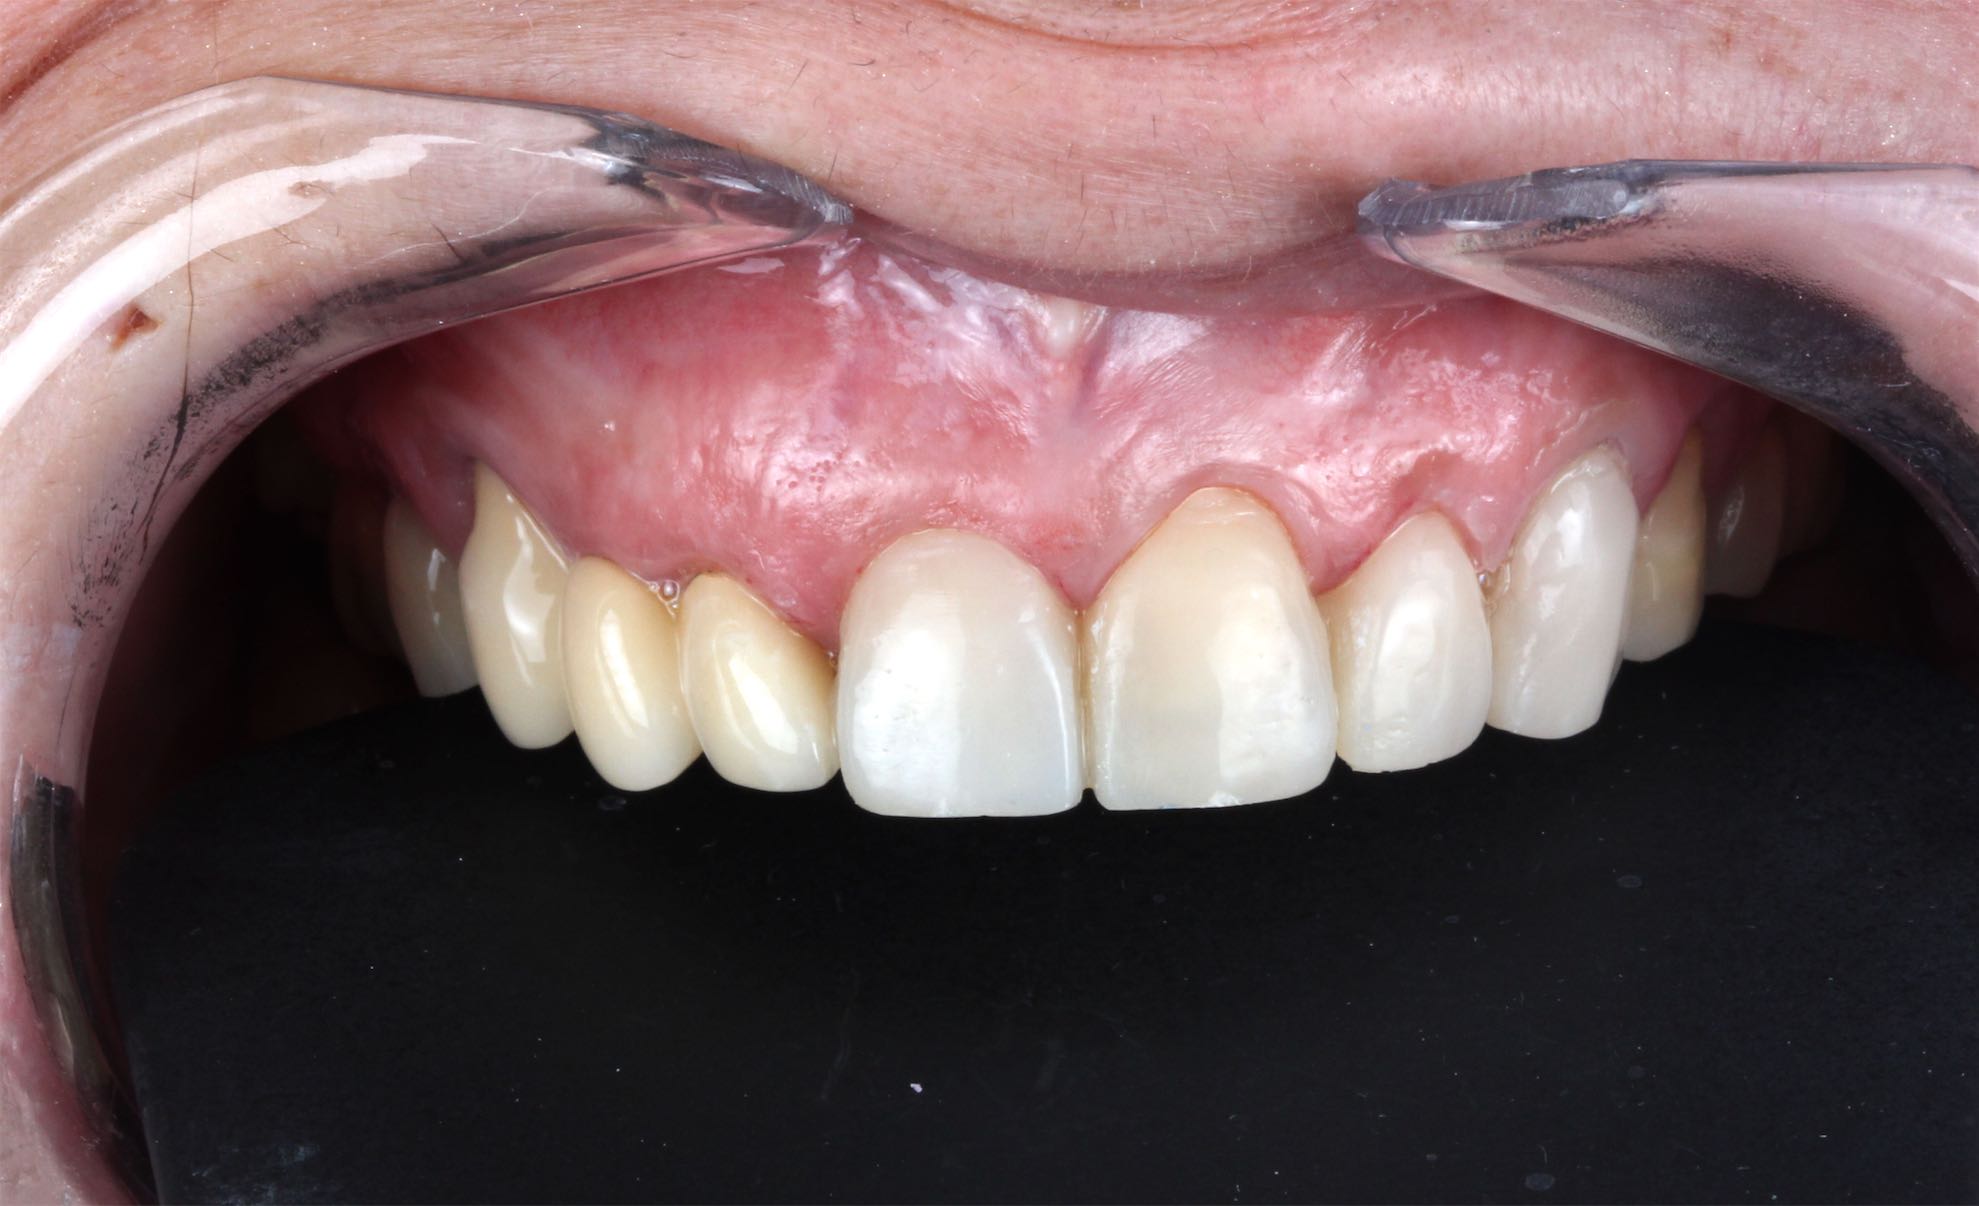

Caso de Rehabilitación completa y aumento de DV

BeforeAfter